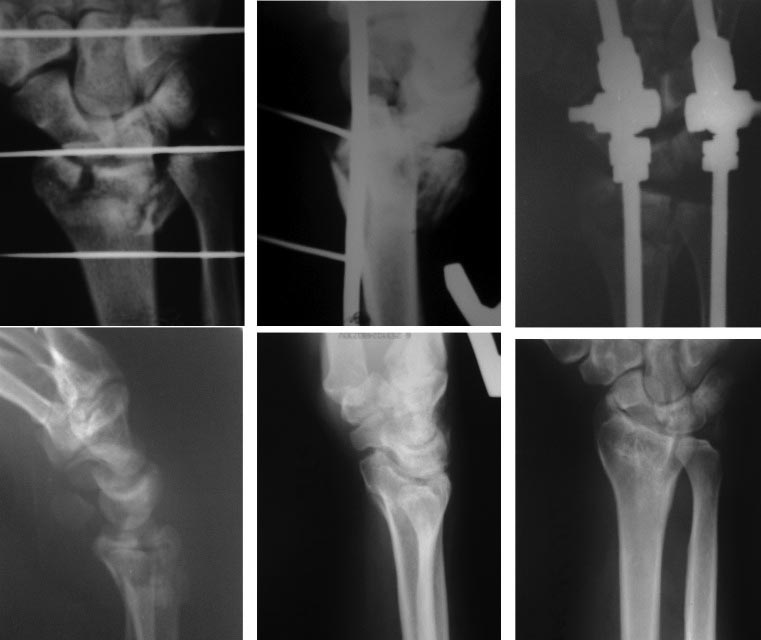

Коллеги дайте совет, что рекомендовать пациенту. травма 8 мес. назад многооскольчатый перелом дистального отдела лучевой кости, репозиция и фиксация в АВФ,

через 6 нед аппарат демонтирован и пациент пропал, нынче ограничение движений тыльное и ладонное сгибание по 15-25, пациент активно занимается бодибилдингом, к занятиям приступил самовольно через 2 мес после травмы.

Особых рекомендаций наверное нет . На R-граммах конечно суставная щель значительно снижена,с явными явлениями ортроза . Снижение объема нагрузок в бодибилдинге т.к. нагрузки на л/зап. суставы там не слабые . И разумное разрабатывание сустава .

Наверное с учетом того,что это спортсмен,то более целесообразно выполнить коррегирующую остеотомию с восстановлением анатомии сустава,фиксацией пластиной для дистального луча с угловой стабильностью. При необходимости использовать костную пластика. Внешнюю иммобилизацию не применять. Ранняя реабилитация.